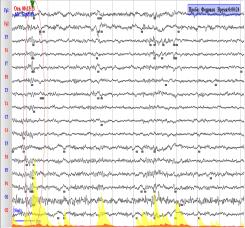

спектральной мощности ЭЭГ. Как пример рассмотрим паттерн аудиосигнала 5 - При

прослушивании отрезка аудио сигнала 5, на ЭЭГ фиксировали уменьшение амплитуды

бетта ритма электрического сигнала на 15%, на фоне роста основной частоты бетта-ритма на 20 % относительно таковых

средних характеристик фоновой записи

ЭЭГ . При влиянии музыкальной композиции «Parov

Stelar – Catgroove»

наблюдалось изменение зонального распределения бетта-ритма и распространению

его без выраженной ассиметрии по неокортексу человека. Для распределения бетта –ритма наблюдается

незначительная его асимметрия, которая составила 1,2% .(Рис.3).

Рис.3.

Пример записи ЭЭГ. Графическое представление записи электрических сигналов

мозга из всех отведений и зональное распределение бетта-ритма по неокортексу

человека. А. Паттерн фоновой

ЭЭГ. Б. Паттерн ЭЭГ на фоне аудио-стимула.